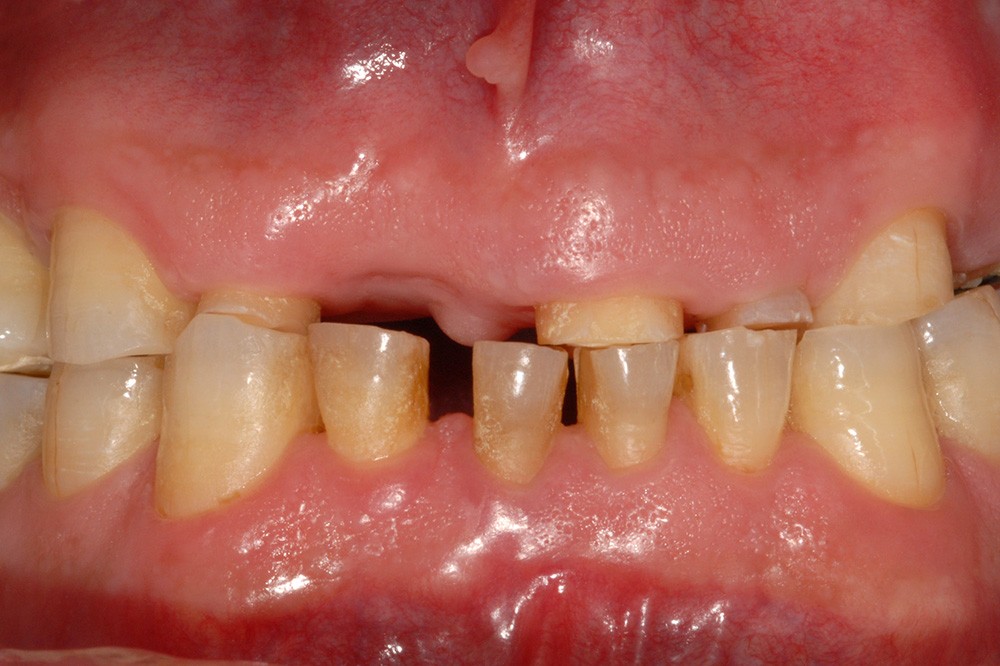

Lorsque l’abrasion est focalisée, en général au niveau cervico-vestibulaire, elle est essentiellement liée au brossage dentaire. Les particules abrasives contenues dans le dentifrice constituent le troisième corps qui s’interpose entre la brosse et les dents. Dans certains cas pathologiques favorisés par un environnement acide, la dentine radiculaire plus ou moins dénudée s’abrase fortement en cas de brossage iatrogène. D’importantes lésions cervicales non carieuses peuvent alors apparaître en peu de temps (fig. 3).